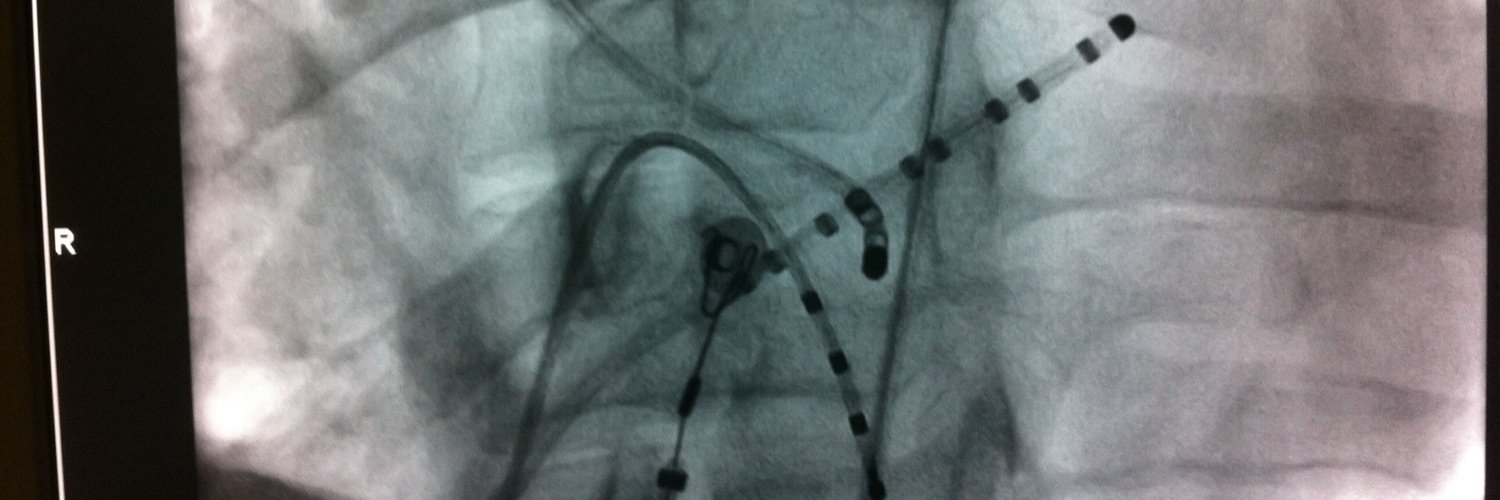

25 y/o with hx of palpitations presented with left ecg to the ER & Cardioverted(Right ecg)

What's the likely Diagnosis?

@ALFIEEP1 @ProfDConnelly @adribaran @SergioPinski @IsaParam @EPWaveDoc @KostekMilan @ArshadEP277 @UlhasDr @DrRoderickTung @DaveRichley @javadm20